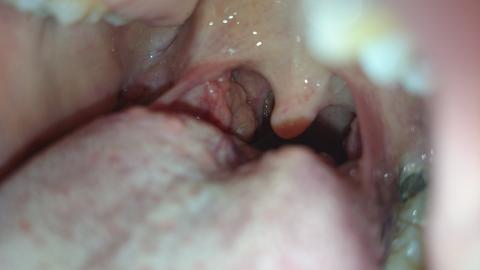

Pro větší náhled klikněte na obrázek

Dobry den, prosim o radu, uz asi tri tydny mam pocit neceho v krku, nejde to spolknout a prekazi to pri jidle. Pri pohledu do krku jsem zjistila ze mam u mandle nejaky vyrustek. Mam to jen na jedne strane. Co by to prosim mohlo byt? Mam hrozny strach z nadoru .. Dekuji za odpoved.

Dobrý den, fotografie není příliš přehledná, ale v oblasti před pravou mandlí se mi zdá drobný váček - cystička. Nejde o nic vážného, většinou je to důsledek nějakého mechanického podráždění, časem to zmizí. Zkuste kloktatdla, např.heřmánkového čaje.